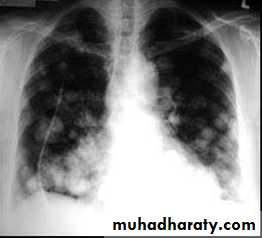

Focal ( Solitary or multiple )Diffuse ( alveolar or interstitial )

>5mm =miliary

Miliary shadow

1) infection ( TB ,fungal , viral )2)Dust inhalation (workers in dust materials)

3) Metastasis

=2-3mm

After treatment

Miliary TB